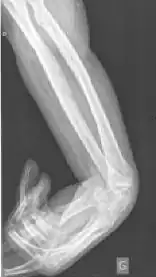

Une contracture sous rayon X